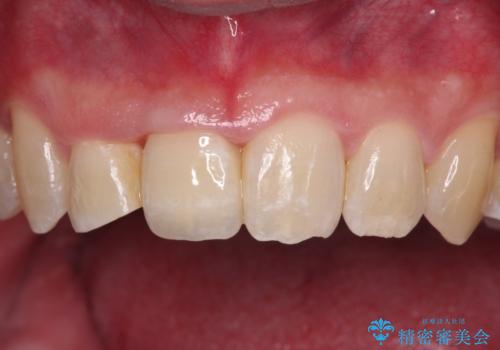

矯正治療後にはオーダーメイドタイプのオールセラミッククラウンを装着し、自然な口元に仕上がりました。